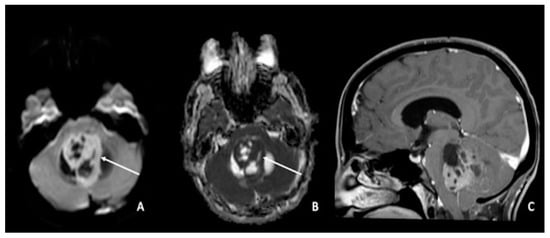

5. Medulloblastomas

2. Gliomas and Cellularity